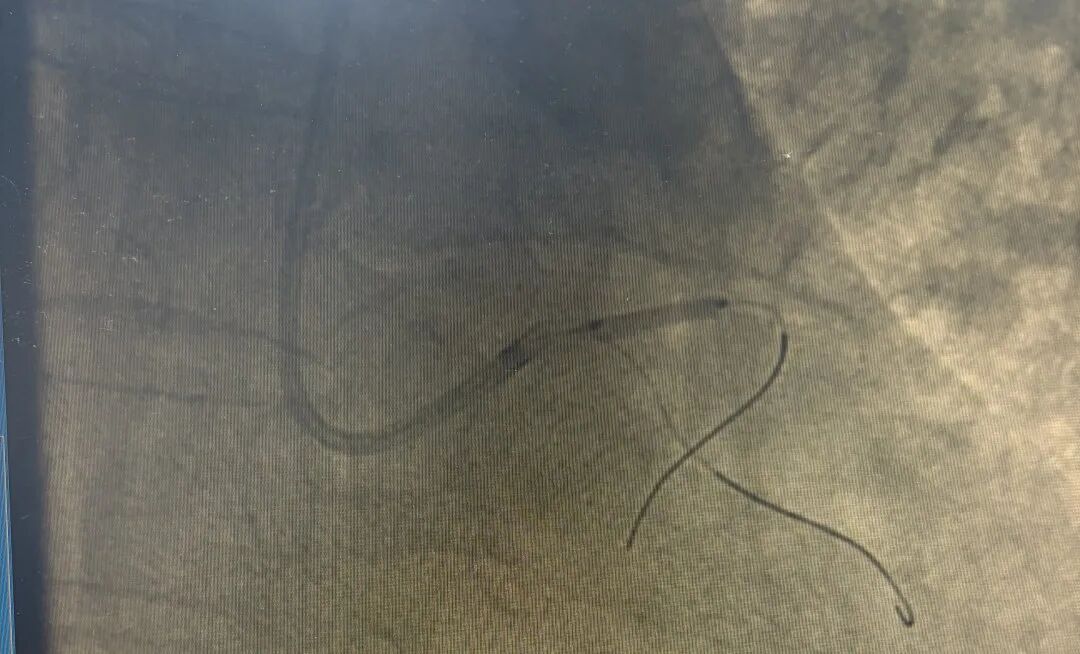

导管室内,冠脉造影屏上触目惊心:左主干本体99%狭窄,前降支血流几乎中断,心肌濒临全面坏死。

冠脉造影(术前)

冠脉造影(术中)